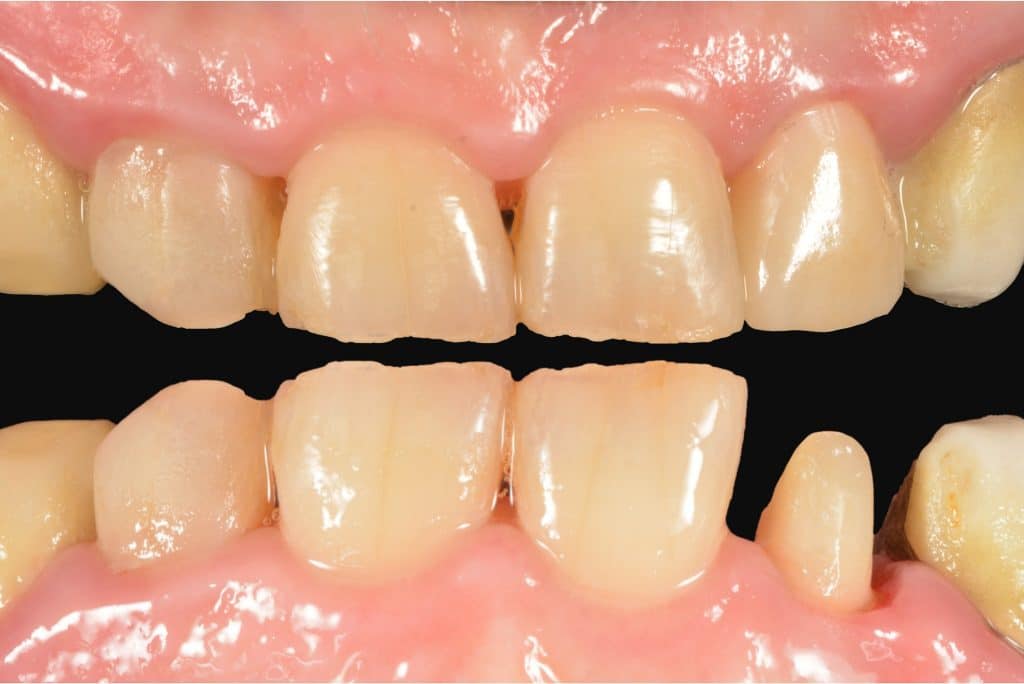

The final restoration, at control, shows a great integration with either soft tissues and teeth.

final

smile

pre and post